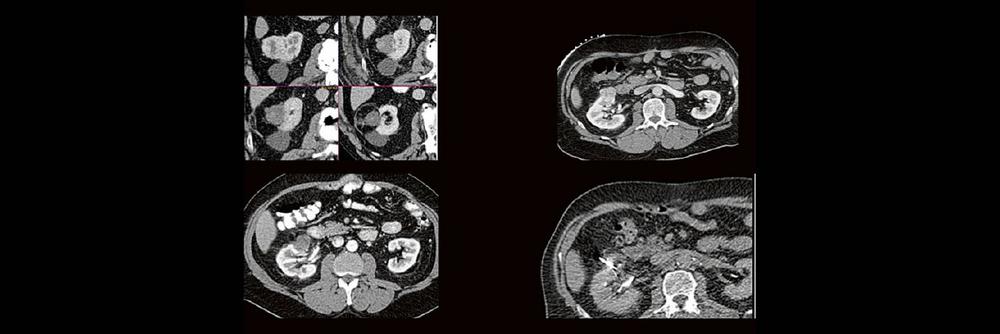

Back to the roots! Gute Kenntnisse der Anatomie sind der Schlüssel zur guten Planung, Durchführung und richtigen Diagnosestellung im CT des Abdomens. Lernen sie unverkrampft

• schnelle Orientierungspunkte für den Alltagsgebrauch

• richtiges Kontrastmittel-Timing im Bild erkennen

• Anatomie in Pathologie übersetzen

Haben Sie es erkannt? Probieren Sie selbst im lockeren Fallquiz zum mitraten.